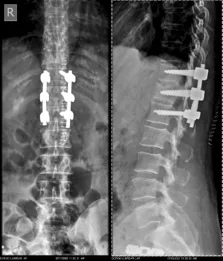

Before & After Clinical Gallery

We showcase real patient cases (with consent), including:

• Pre- and Post-operative MRIs and X-rays

• Disc Herniations, Stenosis, and Spondylolisthesis cases

• Visible improvement in alignment and decompression

Before

After